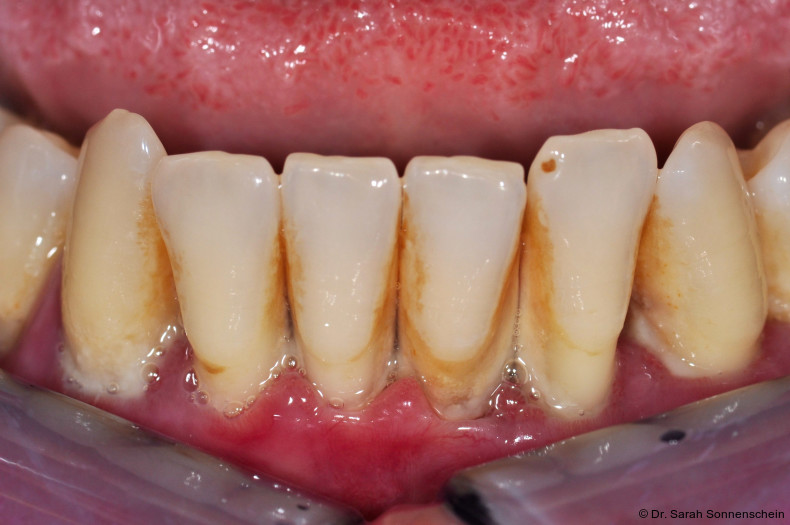

Die im Rahmen eines aktuellen Reviews14 durchgeführte Datensynthese aus zwei retrospektiven Studien zur Schienung parodontal geschädigter und gelockerter Zähne11, 12 kommt zu dem Ergebnis, dass die gewichtete mittlere Inzidenz für Zahnverlust gelockerter und geschienter Zähnen bei 8,4 Prozent innerhalb von zwei Jahren nach nichtchirurgischer Parodontitistherapie lag, wohingegen die gewichtete mittlere Inzidenz für Zahnverlust von den entsprechenden Kontrollzähnen bei 10,1 Prozent lag. In den beiden ins systematische Review eingeschlossenen Studien zeigten die geschienten Zähne im Verlauf der unterstützenden Parodontitistherapie (UPT) stabile parodontale Verhältnisse. Signifikante Veränderungen der Plaquewerte durch die Schienung wurden nicht festgestellt.12 Wird die Schienung aus Stabilitätsgründen über die Schmelz-Zement-Grenze hinaus gestaltet, kann die Konstruktion sogar den positiven Effekt eines Widerlagers für die Interdentalraumbürstchen haben und bei guter Passung die Reinigung für den Patienten einfacher machen. Dies ist besonders bei großen freien Interdentalräumen der Fall. Um den parodontalen Therapierfolg langfristig zu sichern und Karies zu vermeiden, ist nach Einbringen der Schienung eine korrekte Anpassung der Interdentalraumbürstchen für jeden Zwischenraum und die entsprechende Instruktion des Patienten unerlässlich (Abb. 1).

Die Abbildungen 2a–d zeigen die Eingangssituation einer allgemeinmedizinisch gesunden 37-jährigen Nichtraucherin mit Parodontitis Stadium IV Grad C, Falltyp 1 (damalige Diagnose: generalisierte aggressive Parodontitis). Ihr Hauptanliegen war der Zahnerhalt und die Beseitigung der „lockeren“ Zähne. Die Sondierungstiefen lagen generalisiert zwischen 5 und 9 mm. Die AV bei bis zu 12 mm. Die Zähne 33-43 wiesen alle einen Lockerungsgrad III auf. Auch die Oberkieferfront wies einen Lockerungsgrad II auf. Nach der Mundhygienephase erfolgte eine Full-Mouth-Disinfection mit adjuvanter Antibiotikagabe. Die Schienung der Zähne 33-43 erfolgte mittels glasfaserverstärkter Kompositverblockung. Bei Befundevaluation zeigten sich nur noch vereinzelte Taschen von bis zu 5 mm, welche reinstrumentiert wurden. Die Patientin konnte entsprechend in die engmaschige UPT (dreimonatiges Intervall) überführt werden. Zur Verbesserung der Ästhetik und Stabilisierung der gelockerten Oberkieferfrontzähne erfolgte nach Abschluss der aktiven Behandlungsphase ebenfalls eine Verblockung der Oberkieferfrontzähne und Zahnumformung im direkten Verfahren mittels Komposit. Abbildungen 3a–d zeigen die Situation der Patientin zweieinhalb Jahre nach Erstbefundung.